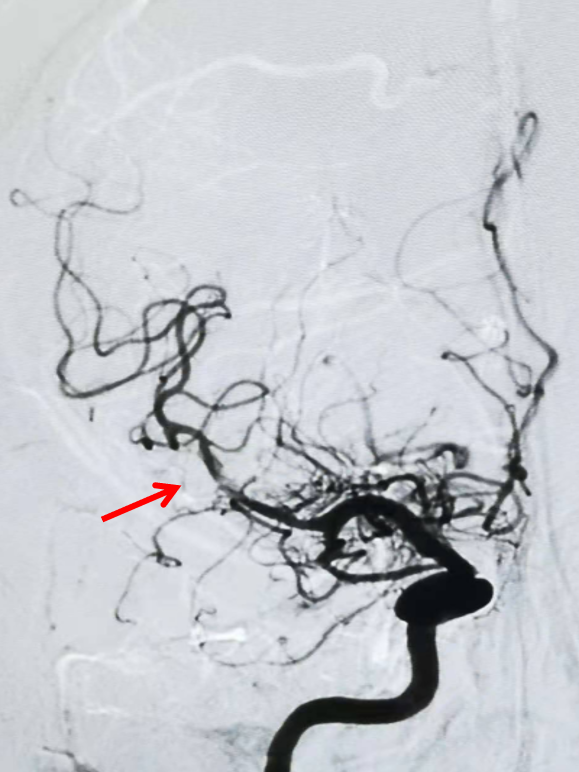

左侧颈总动脉正位造影:双侧大脑前动脉显影,且右侧大脑前动脉通过软膜吻合向右侧大脑中动脉支配区域供血(箭头示)。

中间导管到位后造影,提示右侧大脑中动脉M1段闭塞,右侧大脑中动脉供血区域通过右侧大脑前动脉软膜支部分代偿。